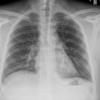

Lymphoma PA (DLBC)

Date: 04/25/2009

Views: 3543